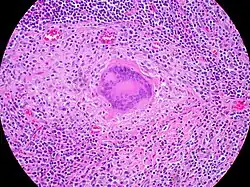

![]() |

Follicular lymphoma | Micrograph showing a small B-cell lymphoma compatible with follicular lymphoma. H&E stain. | Category: Histopathology of follicular lymphoma | Follicular lymphoma |